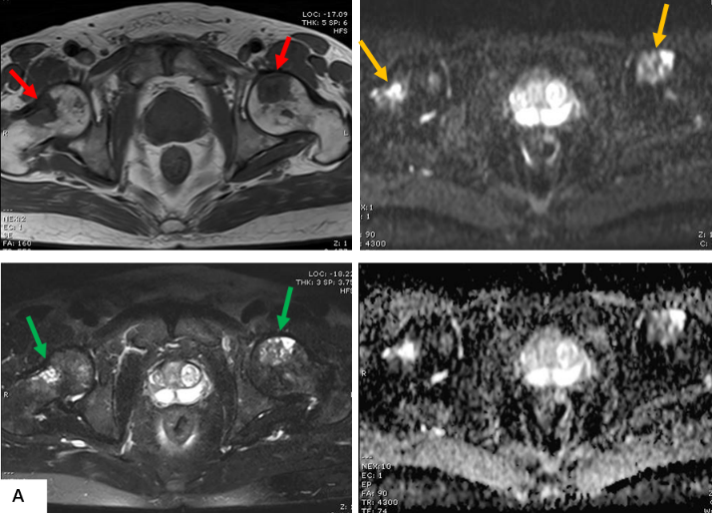

前列腺MRI示:前列腺移行帶結節狀異常信號,建議穿刺活檢;前列腺增生,PI-RADS2;雙側股骨頭信號異常,不排除轉移瘤(圖A)。為評估骨轉移情況遂行ECT全身骨顯像檢查,示:雙側肱骨頭、雙側股骨頭、右側前臂上段、右側股骨中下段代謝異常增強(圖B)。骨顯像不符合前列腺癌骨轉移典型表現,同時結合患者胸部CT(圖C)平掃示右側腋窩多發淋巴結腫大,生化檢查示乳酸脫氫酶620U/L(97-270),懷疑系血液系統腫瘤,建議患者行PET/CT檢查。PET/CT示:右側腦室內高密度灶,多發FDG代謝增高淋巴結及多發骨骼/骨髓FDG代謝增高灶,考慮淋巴瘤(圖D)。

MR示雙側股骨頭見斑片狀壓脂高信號(綠箭),T1WI信號減低(紅箭), DWI呈混雜高信號(黃箭)。